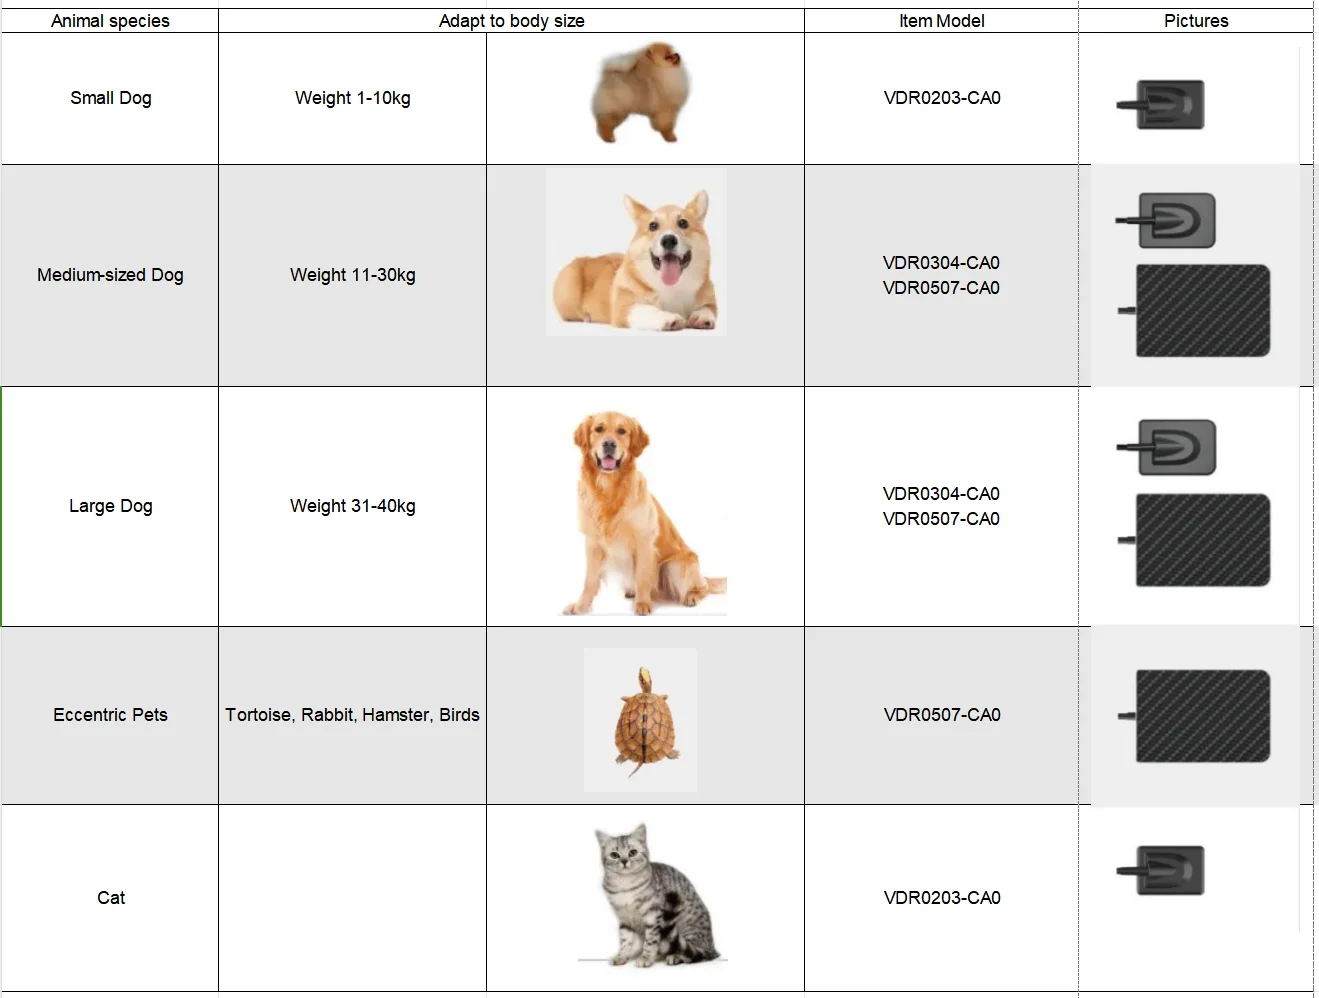

CE Approved Original HANDY Size 4 Dental X Ray Sensor Large Size Veterinary Sensor for Medium and Large Dogs

Model Number | VDR0507-GA0 |

Effective area | 46.7*67.3mm |

Dimensions | 77.1*53.8mm |